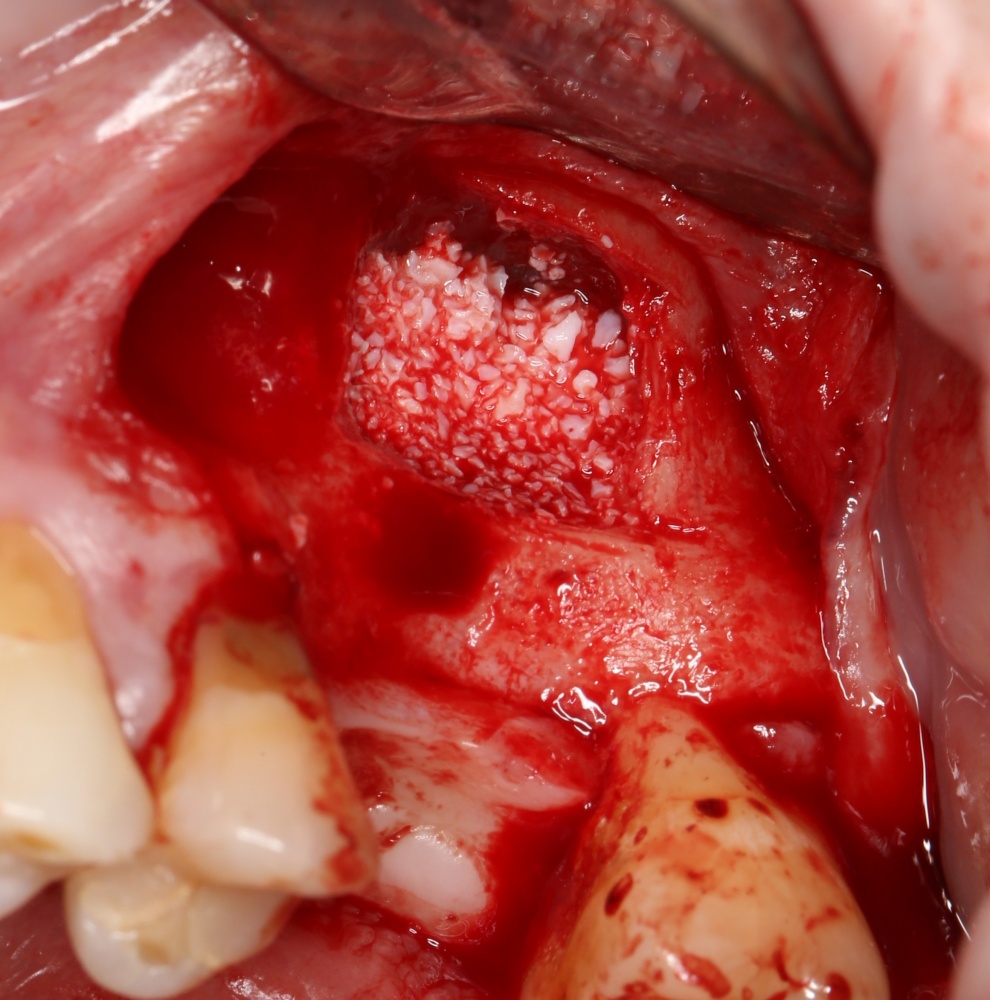

Простой синуслифтинг. Часть I.